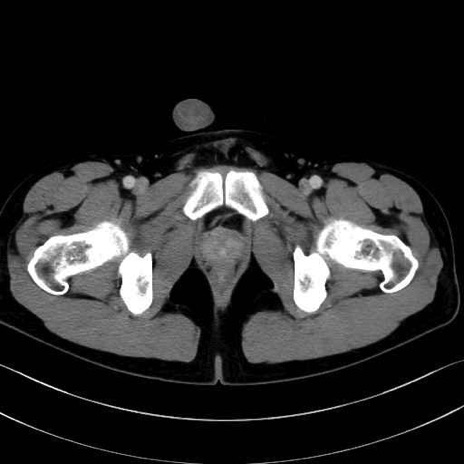

大内転筋・小内転筋 (Adductor magnus / Adductor minimus)